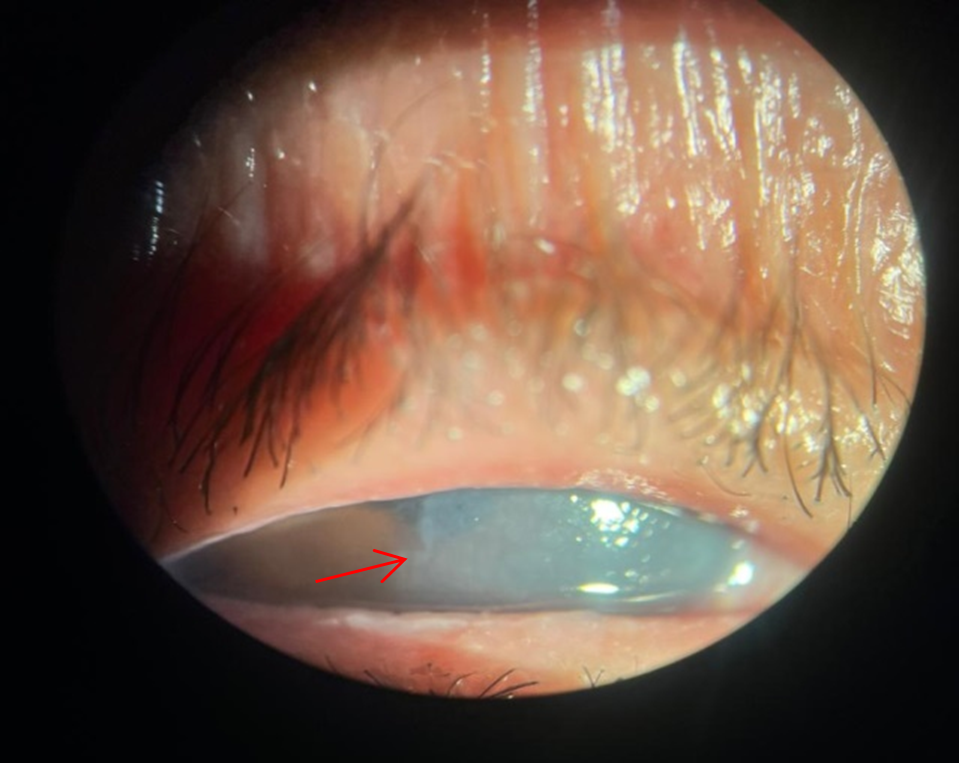

On postoperative day one, the patient presented with counting fingers visual acuity, epiphora, and marked corneal edema involving nearly two-thirds of the lateral cornea (Figure 1). Intraocular pressure was 16 mmHg.

Figure 1: Slit-lamp image of the right eye on postoperative day one showing extensive corneal edema corresponding to the zone of Descemet’s membrane detachment (DMD). The red arrow indicates the margin between the clear cornea and the ruptured zone of Descemet.